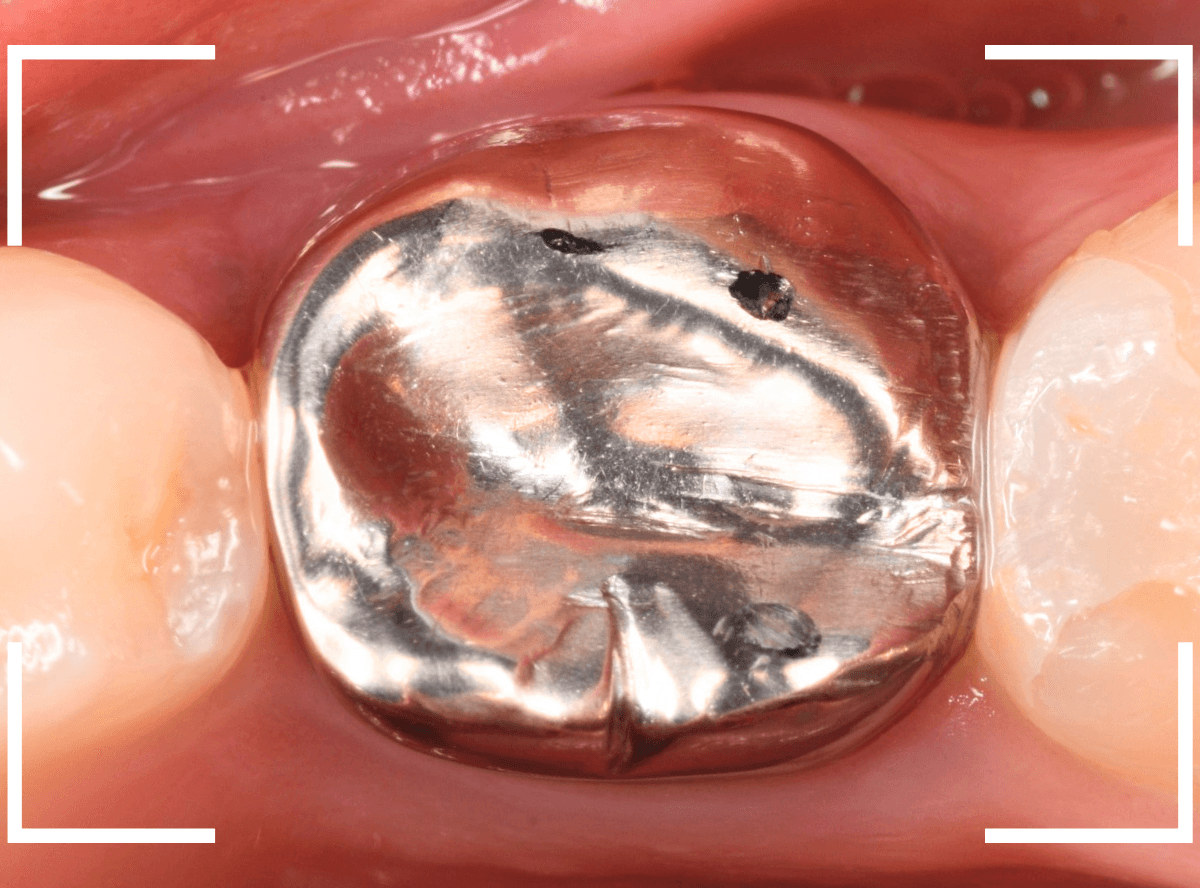

メタル・インレーとメタル・クラウンが入っていますね。

まずは、奥のメタル・クラウンを外します。

メタル・コアが入っていますが、こちらも慎重に外して、中を調べていきます。

レントゲン写真では問題なさそうでしたが、メタルコアを除去すると、中は真っ黒でした。

このように、コアの中で虫歯が進行している場合もありますので、さし歯をやり直す際は、出来る限りコアも外して調べるようにしています。